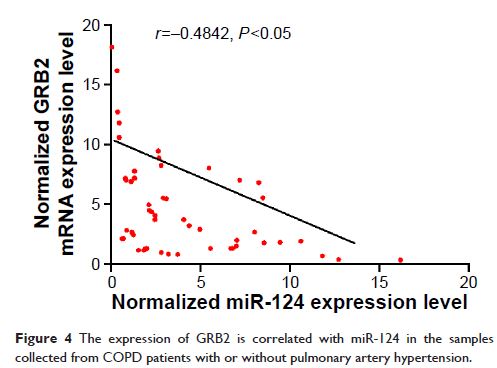

Original Research

Pri-microRNA-124 rs531564 多态性次要等位基因通过肺动脉平滑肌细胞增殖的异常强化,增加了肺动脉高压的风险

- 作者:Quanzhong Li, Zongjie Qian, Linqing Wang

- 期刊:International Journal of Chronic Obstructive Pulmonary Disease